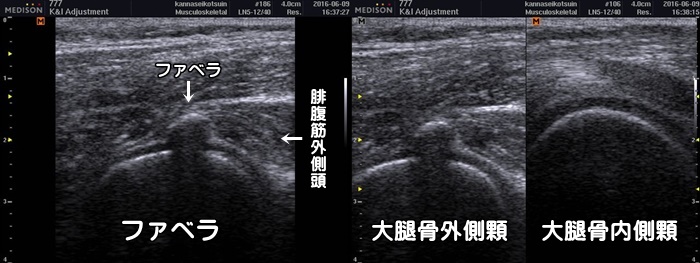

ファベラ(膝窩部痛)

ファベラとは膝裏の外側(腓腹筋外側頭内)にある種子骨と呼ばれる小さな骨です。全員に存在するわけではなく、報告により約10~15%の方に存在します。ファベラが存在してもほとんどの場合、症状はありません。しかしごく稀に①ファベラにおける鋭い疼痛②限局した圧痛③膝伸展時痛の3症状がみられる場合はファベラ症候群を疑います。膝裏のストレッチを続ける事で痛みは消失しますが、頑固な痛みに対しては摘出術が行われる場合もあります。